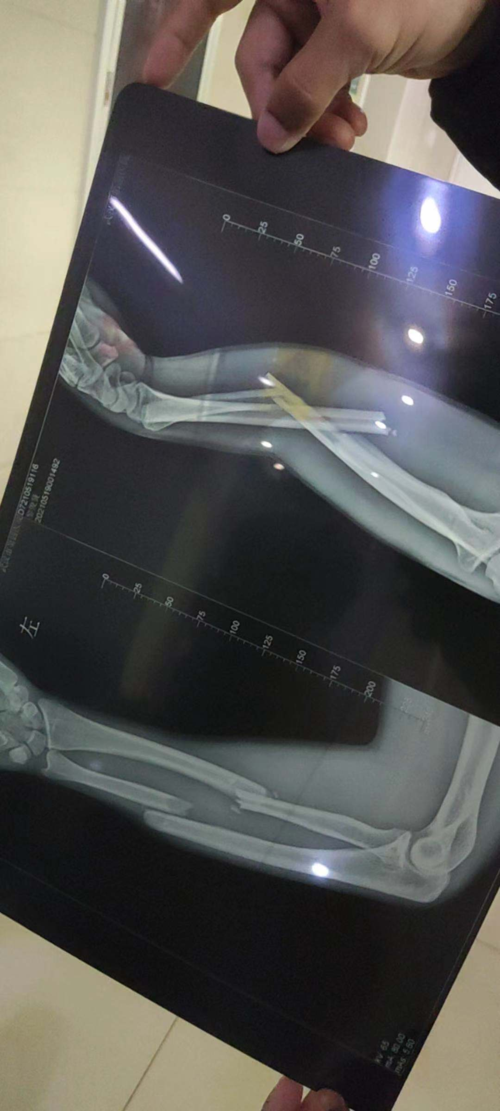

胳膊肘饶骨小头骨折,疑似鹰嘴也骨折,这是带支具一个月拍的片子,请问

骨折的x光片

拍摄的吴菊萍受伤左臂的x光片,医生诊断为手臂左尺桡骨多段粉碎性骨折

请问大家,这张片子出,是骨折了吗?

尺桡骨中段骨折